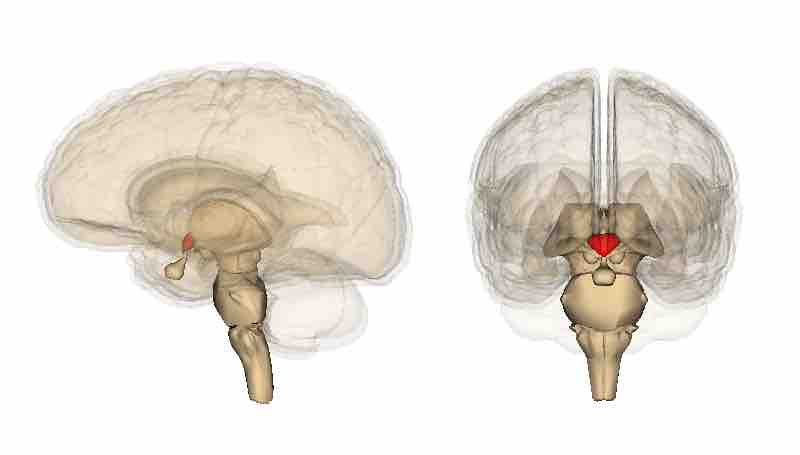

The Endocrine System and Hunger

Hypothalamus

The hypothalamus is the region of the forebrain below the thalamus that forms the basal portion of the diencephalon. It regulates body temperature and some metabolic processes, and governs the autonomic nervous system.